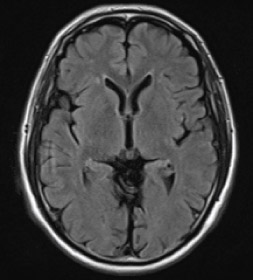

頭部MRI

頭部の断面を画像化して、脳梗塞や脳出血などの頭部疾患の有無や脳腫瘍の大きさを判別することが可能です。